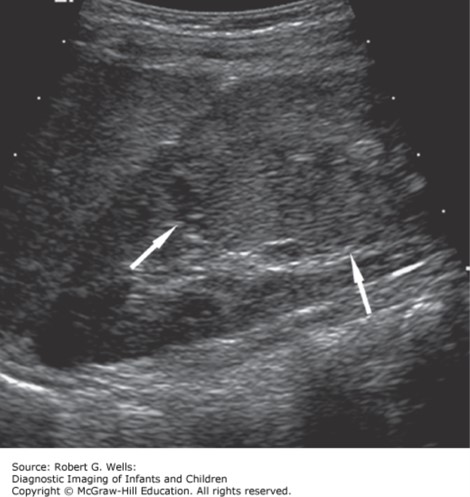

The correct answer is “A.” Painless gross hematuria in a toddler or preschool-aged child, even when intermittent, is highly suspicious for Wilms tumor (WT). A newly-identified abdominal mass is often palpated, and sometimes is the only finding, incidental on a well-child visit, that identifies this tumor. Because the tumor is not adjacent to the diaphragm, it does not move with respirations as an enlarged spleen does (making option “C” incorrect). Associated symptoms for WT are based on mass effect and may include constipation (constant or intermittent) and bladder dysfunction. Staging workup includes CT scan of the chest, abdomen, and pelvis; local extension and distant metastasis—often to the lungs—are both hallmarks of this disease. Therapy includes upfront resection of the affected kidney, followed by chemotherapy and radiation therapy dictated by stage. Cure rates for the most common forms of WT are excellent, well above 90%. Distinguishing WT from neuroblastoma (option “B”), another frequently encountered abdominopelvic tumor in the same age range, is not reliably done by physical exam or ultrasound. CT scan may be helpful, as neuroblastoma tends to exhibit calcifications, while WT arises within the kidney and pushes renal parenchyma toward the capsule. (See Figure 4–2.) Tissue diagnosis is required to be certain. Rhabdomyosarcoma (RMS; option “E”) is a soft tissue sarcoma that may arise in nearly any tissue of the body. In boys, it is frequently found arising from the prostate or bladder, which would be unexpected to exhibit a flank mass if involving the midline urogenital system. RMS is also less common overall than WT. Finally, while pyelonephritis (option “D”) may exhibit renal complications, the overall well appearance of the child and presence of a mass are not consistent with this diagnosis.

Photo: Wells RG. Diagnostic Imaging of Infants and Children; 2015.